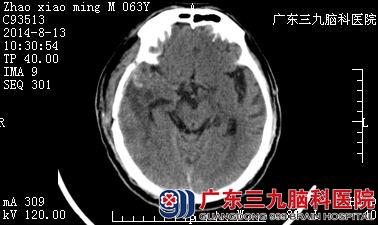

赵伯,今年63岁,家住广东台山,数月前的一天晨起活动时突发头痛,后晕厥过去,被家属紧急送至当地医院。测血压示190/105mmHg,头颅CT检查示:右侧颞叶脑出血。当地医院给予脱水降颅压、控制血压等积极处理后,赵伯的病情稍好转。为求进一步治疗,家属于2014年8月5日将赵伯转入广东三九脑科医院。

入院查体,赵伯神志不清,嗜睡状,并伴随左侧的肢体乏力。DSA检查示:右侧颞叶血管畸形。诊断:1、右侧颞叶血管畸形并脑出血;2、脑疝;3、高血压病3级(极高危组)。住院后,神经外三科为其行DSA栓塞术,考虑颞叶血肿导致脑疝,遂急诊下行右侧颞叶血肿清除术+畸形血管团切除术。术后患者恢复良好,予以神经营养、康复治疗等。经住院44天,赵伯神志清楚,对答可,左侧肢体肌力5-级,张力不高,病情好转出院。

▲术前